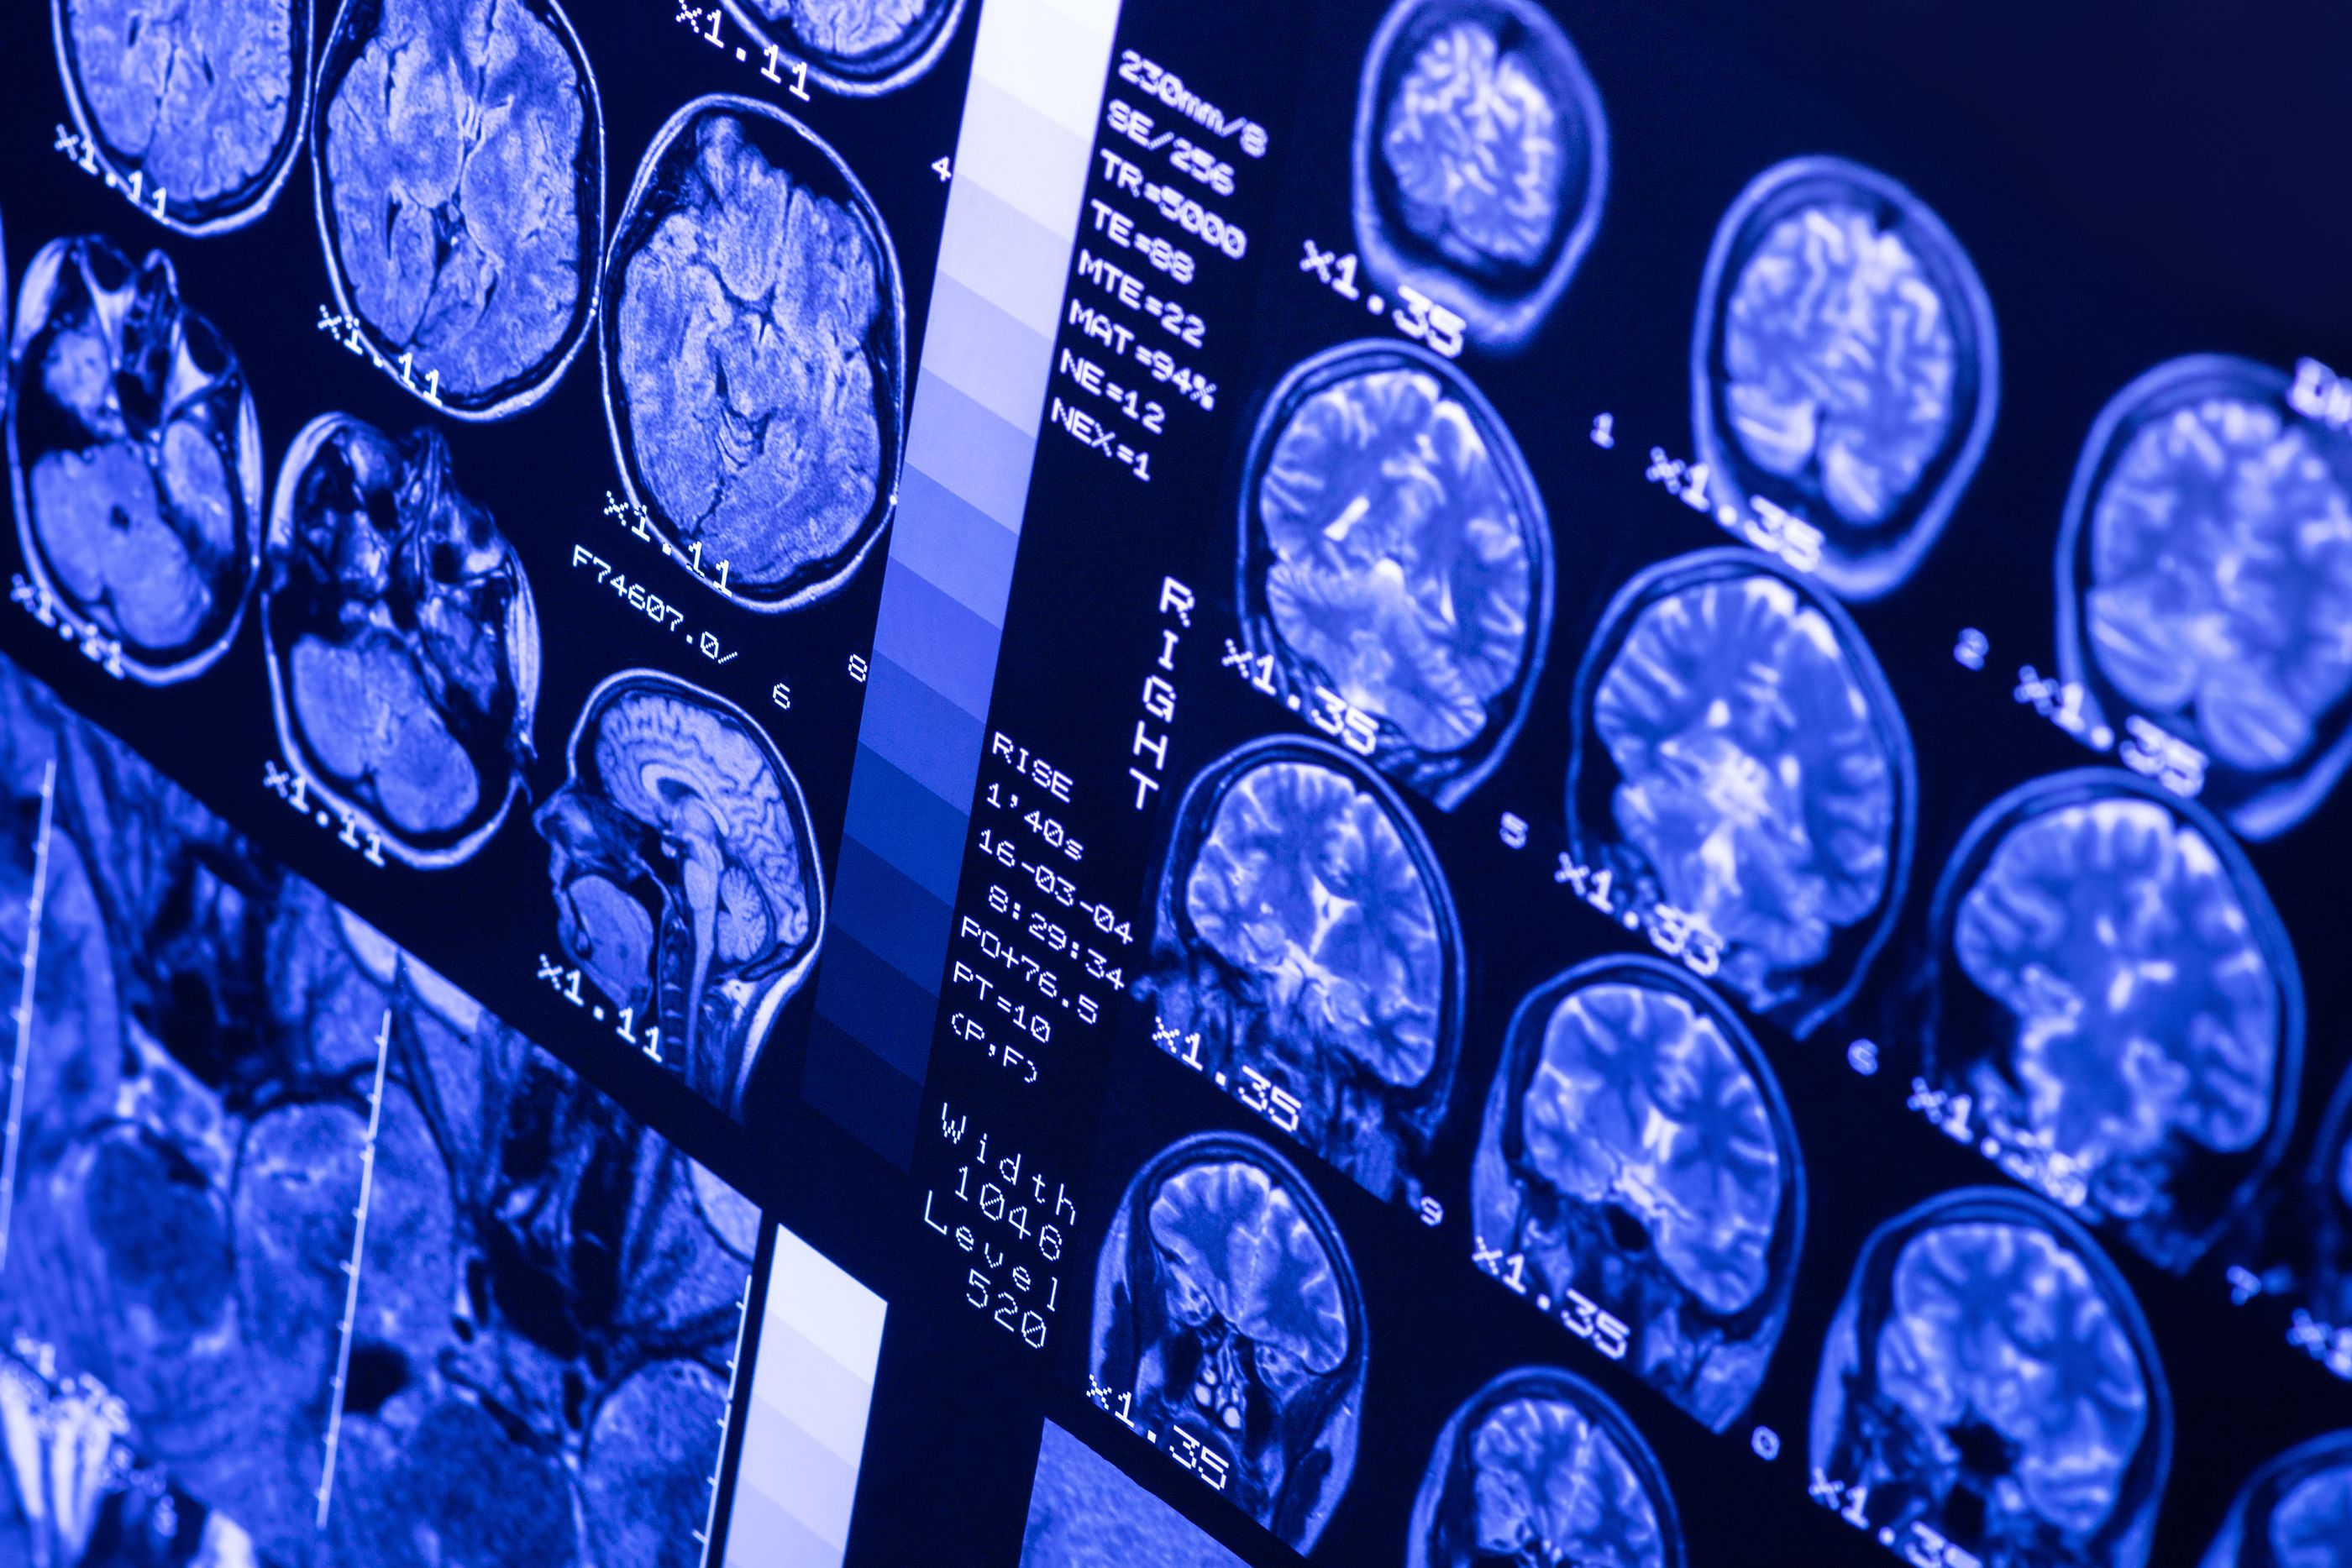

Científicos del Imperial College de Londres han logrado acelerar la detección del alzhéimer a través de la combinación de escáneres con inteligencia artificial, lo que ha demostrado ser eficaz en el 98% de los casos, incluso en las fases más prematuras. Esto supone una doble hazaña, ya que además de ganar tiempo para tratar la enfermedad en los pacientes es posible investigar la enfermedad desde fases tan iniciales que permitirán a los científicos precisar aquellos aspectos de la enfermedad imperceptibles para las capacidades humanas.

El objetivo era aplicar un algoritmo que ya se estaba aplicando en la detección del cáncer adaptándolo a los escáneres cerebrales. Para ello, dividieron el cerebro en 115 regiones y asignaron 660 características diferentes ( como tamaño, forma y textura) para evaluar cada región. Después entrenaron al algoritmo para identificar dónde los cambios en estas características podrían predecir con precisión la existencia de la enfermedad de Alzheimer.

Durante el experimento se aplicó el algoritmo entrenado a 400 escáneres de cerebros de pacientes sanos, pacientes en fase temprana y avanzada del alzhéimer y personas con otras enfermedades neurológicas, como la demencia frontotemporal o el Parkinson. En el 98% de los casos el algoritmo logró detectar el alzhéimer y en el 79% de los casos incluso pudo diferenciar en qué etapa se encontraba la enfermedad.

Otra ventaja de este método es que su aplicación médica tendría un coste insignificante, ya que lo único que sería necesario es introducir el algoritmo en el escáner estándar de resonancia magnética que incluyen comúnmente casi todos los hospitales.